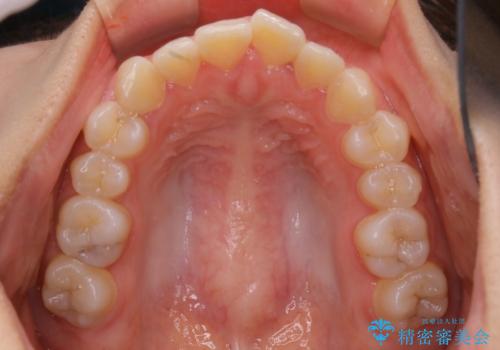

前歯のがたつきをインビザラインで治療

- 上下前歯のがたつきが気になるとの事で来院された患者様です。がたつきの程度が軽度であったため、インビザラインライトにて治療をおこないました。

がたつきの程度が軽度であったことと、インビザラインを正しく装着して頂けたことで短期間で治療終了することが出来ました。